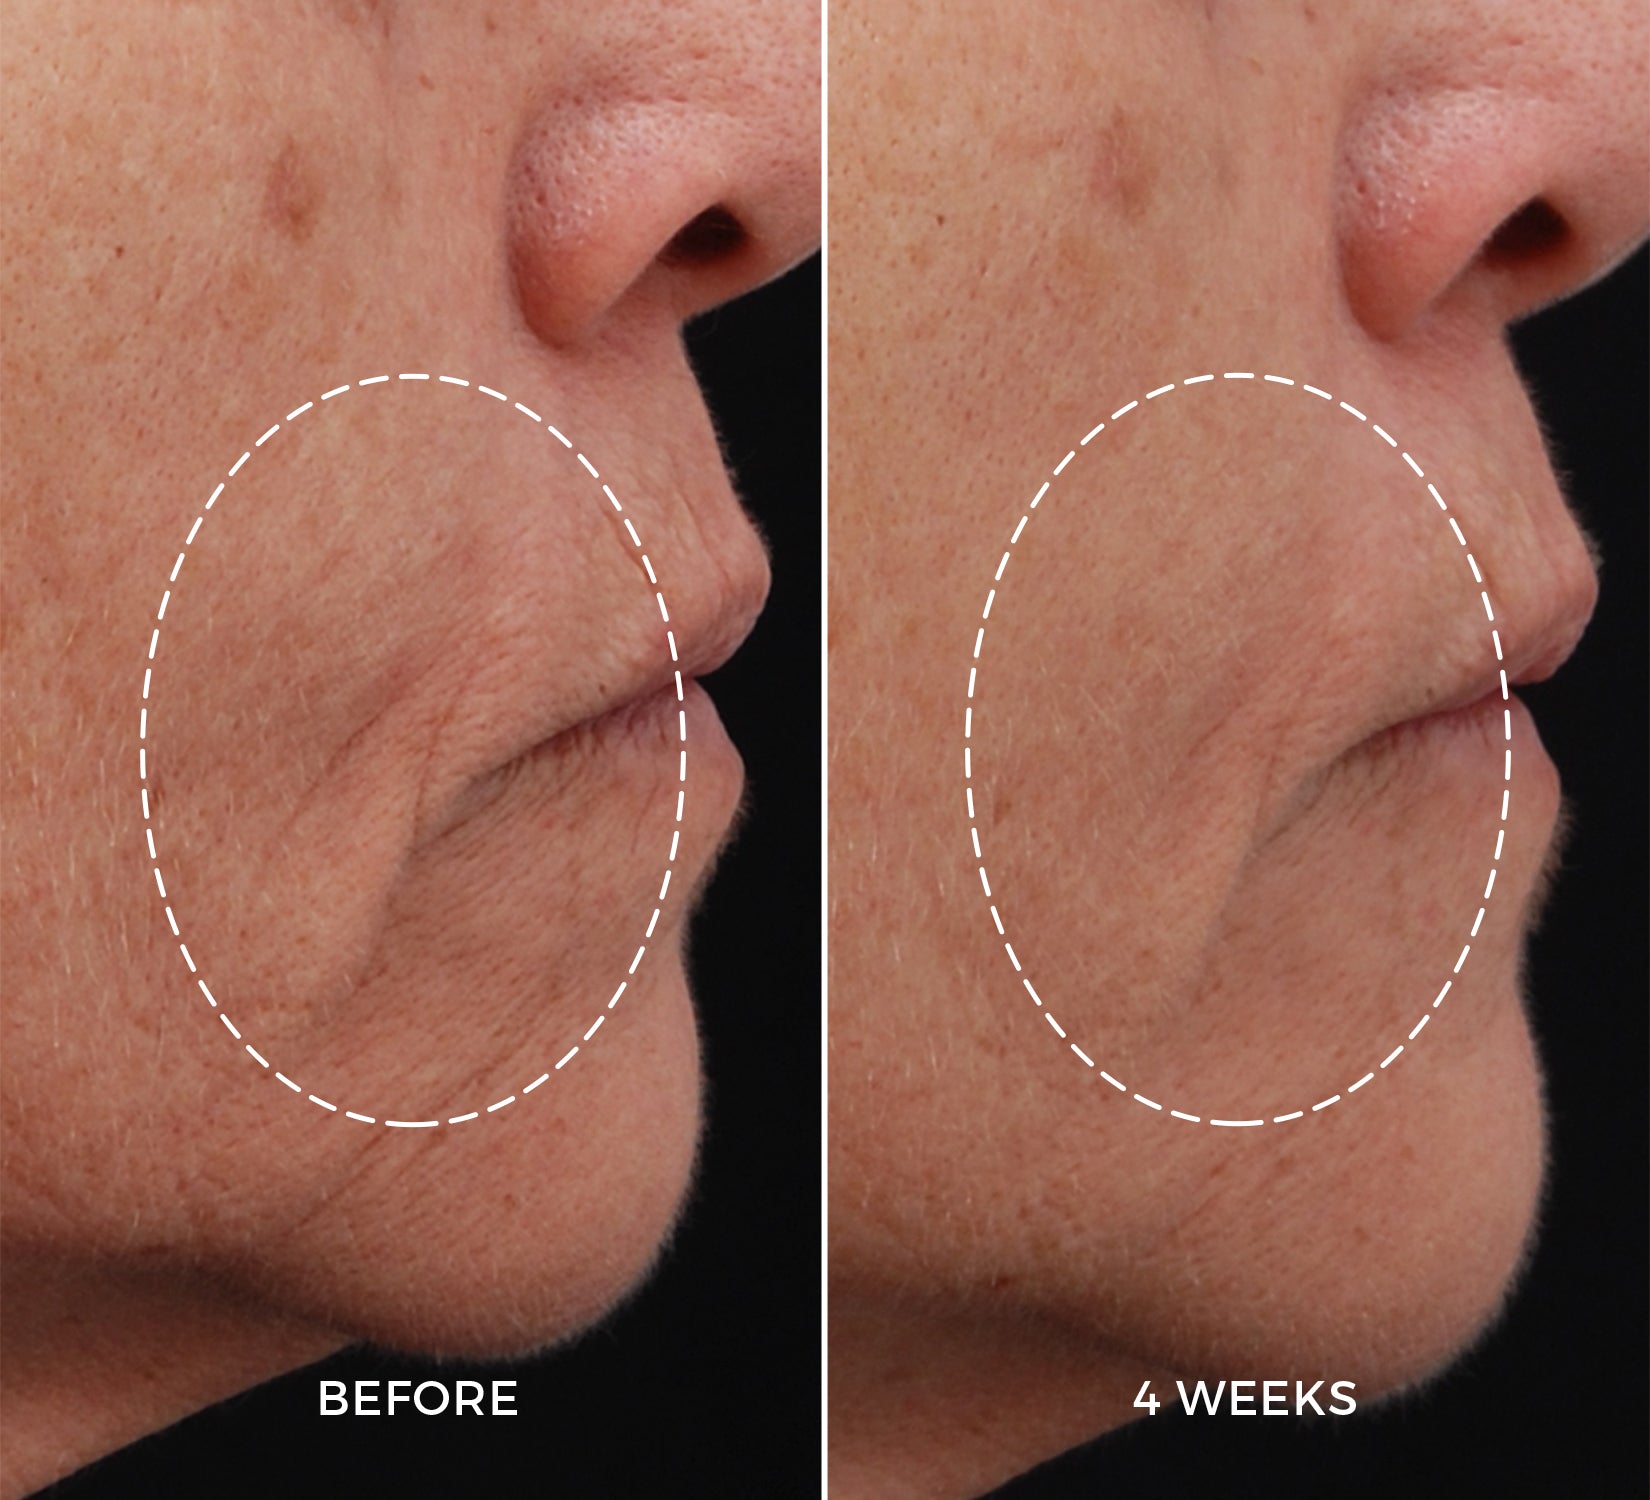

Cheek

The benefits of the NEWA device and NEWA Lift Gel on the skin’s collagen production were clinically tested on participants of various skin types aged 37 to 65. Over a period of three months, individuals who took part in the study used the NEWA combination 3 times a week for the first 4 weeks and twice a week for the remaining 8 weeks. The results were assessed by dermatologists.²

of participants showed improvement in overall wrinkle appearance.

of participants showed improvement in skin firmness.

of participants showed an increase in skin collagen content